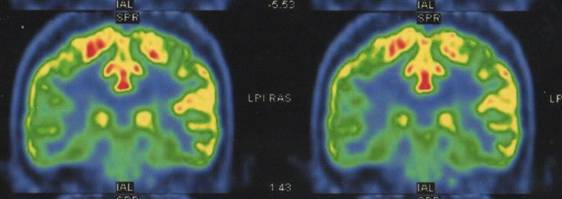

PET/CT:右侧颞枕叶及双侧顶叶多发糖代谢减低灶,以右侧颞叶为著